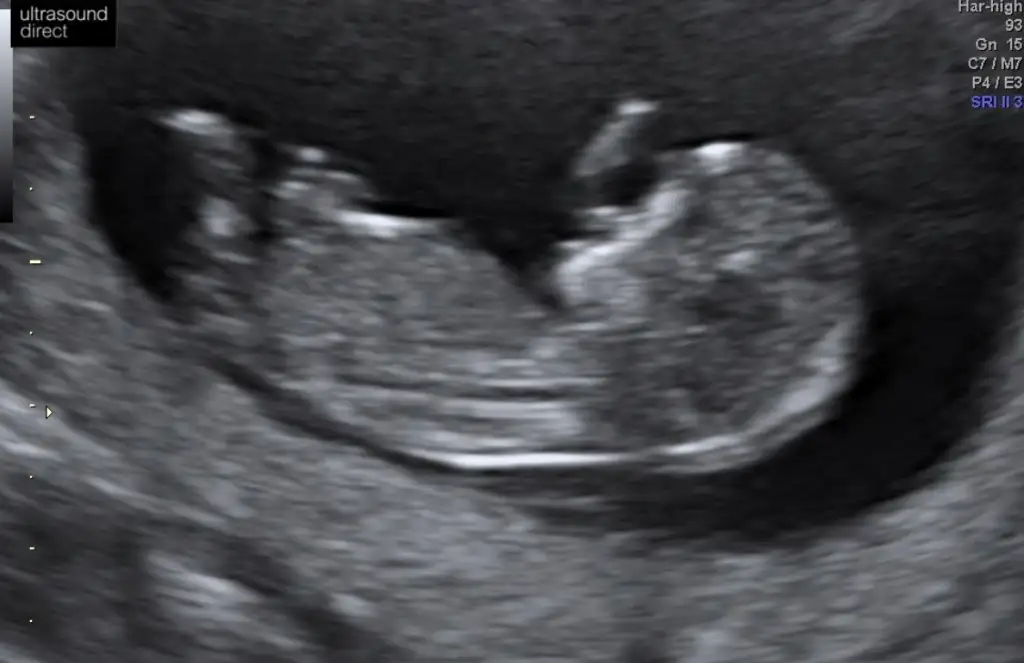

Anket Nub teorosi dogru tahminmi arkadaşlar

Nu teorisi dogrumu yanlışmı

Valla dün 15+0 dı doktor hala yüzde yüz kız demedi 80 diyor:) ama zannetmiyorum değişeceğini daha öncede kız gibi demişti başka bi doktor